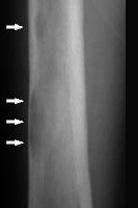

问题 下列哪项X线表现对甲状旁腺功能亢进症有诊断价值()

选项 A.弥漫性脱钙 B.纤维囊性骨炎 C.骨囊肿样变化 D.骨膜下皮质吸收、颅骨斑点状脱钙 E.多发性骨折或骨骼畸形

答案 D